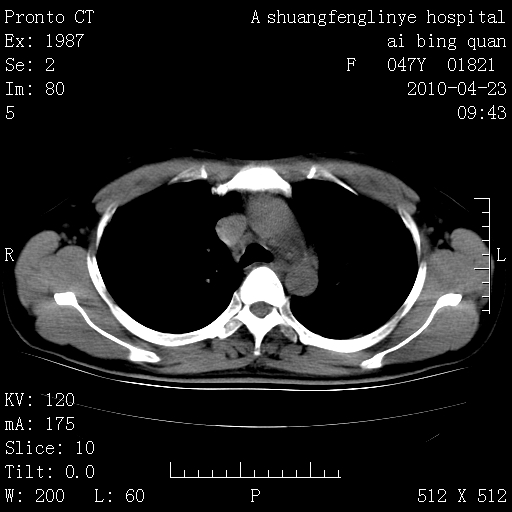

标题: CT25944:胸痛、气短、前几日高烧!肺Ca?请会诊! [打印本页]

标题: CT25944:胸痛、气短、前几日高烧!肺Ca?请会诊!

kaolv 周围型肺癌并同肺转移

双肺多发结节,考虑转移瘤,肺癌肺转移不除外

周围型肺癌并肺转移

双肺多发结节,部分密度较高,最大结节边缘光滑。临床有“胸痛、气短、前几日高烧”病史。首选考虑:右肺感染性病变!建议积极消炎后复查!